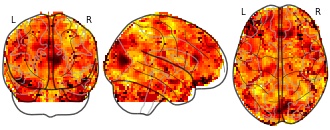

"name": "VBM_HeterogeneityMap",

"description": "Abnormal gray matter in BPD. Brain regions with significant heterogeneity (i.e. between-study variance) in the comparison of patients with BPD and healthy controls. Results are thresholded at at p<.005 & k>20. Note: Results are based on meta-analysis of group comparisons. Note2: Results were updated (see Erratum for this publication)",

"add_date": "2016-01-21T18:23:32.131003+01:00",